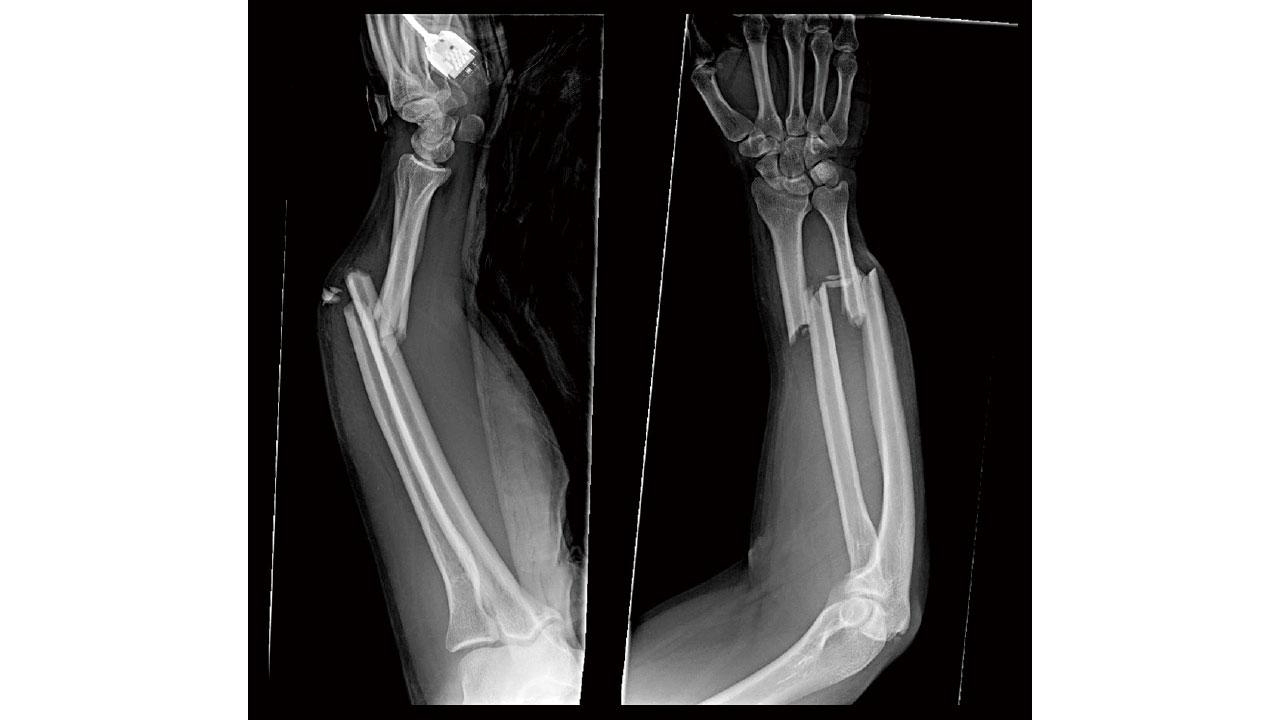

「從X光可見,允行右手前臂的兩條骨,即是橈骨和尺骨,都出現骨折並且移位。幸好骨折並沒有刺穿皮膚,但必須盡快做手術,將骨折復位,用鋼針固定,然後打石膏讓骨折在四至六星期內愈合,最後便可拆石膏和移除鋼針。」當骨科醫生向他母親講解手術時,我緊貼著他的胸膛,聽得到他怦怦的心跳聲,正如他面對著幼羚時害羞的反應。